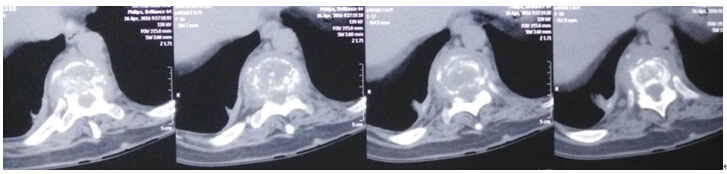

2016年4月29日我科应用椎间孔镜技术、经皮椎弓根螺钉技术成功治疗1例胸椎结核病例。患者女性,67岁,因“胸背部疼痛2月余,加重1月”就诊,经门诊就诊后积极抗结核治疗3周住院治疗。入院患者胸背部疼痛明显,CT示T10、T11椎体骨质破坏,T10塌陷。经科室讨论后应用经皮椎间孔镜技术经椎间孔入路行病灶清除、颗粒骨植骨,再经后路经皮椎弓根螺钉固定。手术顺利,无并发症,目前患者病情平稳。

术前影像学资料